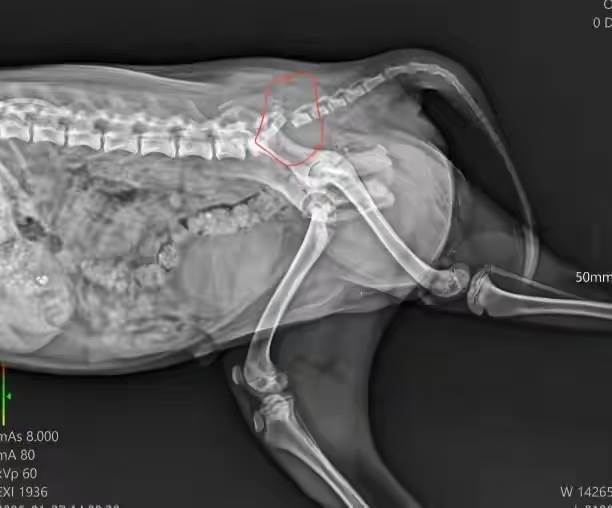

到了寵物醫院,醫生趕緊給小狗做檢查,拍片結果出來后,醫生皺著眉說:「右前腿粉碎性骨折,得馬上做手術,還要住院觀察一周,加上后續的消炎和康復治療,費用大概要五千塊。」 林曉愣了一下 —— 五千塊對剛工作沒多久的她來說,差不多是大半個月的工資,可她看著病床上縮成一團的小狗,沒絲毫猶豫:「醫生,麻煩您盡快安排手術,費用我現在就交。」